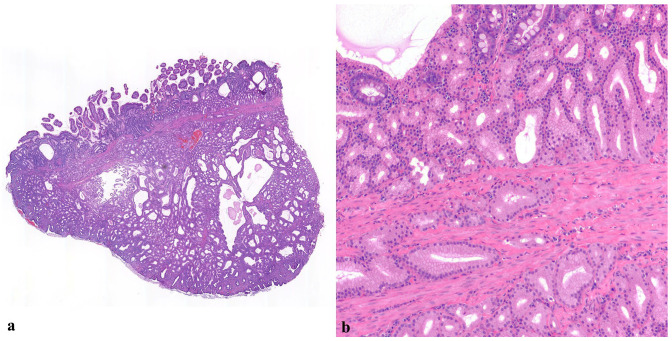

Case series summary: Two cats, aged 13.5 and 14 years, presented with duodenal masses ultimately diagnosed as Brunner's gland (BG) adenomas. In the first cat, the lesion was a firm, pale tan, proximal duodenal polyp adjacent to the major duodenal papilla that was composed histologically of a well demarcated, expansile mass of well-differentiated BGs separated by fibrovascular septa and few adipocytes. This patient was euthanized for otitis-related vestibular signs, and the clinical significance of the duodenal polyp is unknown. The second cat presented with a 6-month history of vomiting. This cat had a mural duodenal mass in the region of the major duodenal papilla of approximately 2 cm, which was histologically composed of a dense population of variably ectatic BGs expanding the submucosa and lamina propria. This patient's mass was non-resectable, but the vomiting resolved after palliative gastroenterostomy loop surgery to allow ingesta to flow past the mass. The patient survived 35 months after the procedure.

Relevance and novel information: BG adenoma is a rare, typically benign tumor in humans with non-specific clinical manifestations and no clear etiopathogenesis. This lesion, and the related condition BG hyperplasia, has been documented rarely in animals (one dog, two horses, and in mice and rats). This is the first description of the lesion in the cat. The comparative pathology, differential diagnoses and possible significance of these lesions are discussed.